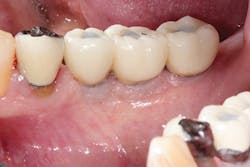

The most critical aspect of any implant system is the interface between the implant fixture and its surrounding bone (figures 1-5). Integration between the fixture and its surrounding bone is the foundation of modern implant dentistry. There is little we can do to modulate bone healing, but we can modify the implant fixture itself.

Figures 1-5: Figures 1 through 4 illustrate, respectively, a seven-year follow-up visit and a three-year follow-up visit of two different implant systems. Implant No. 22 (figure 5) shows peri-implant radiolucency following functional loading, indicating fibroencapsulation and loss of integration into bone, necessitating removal.